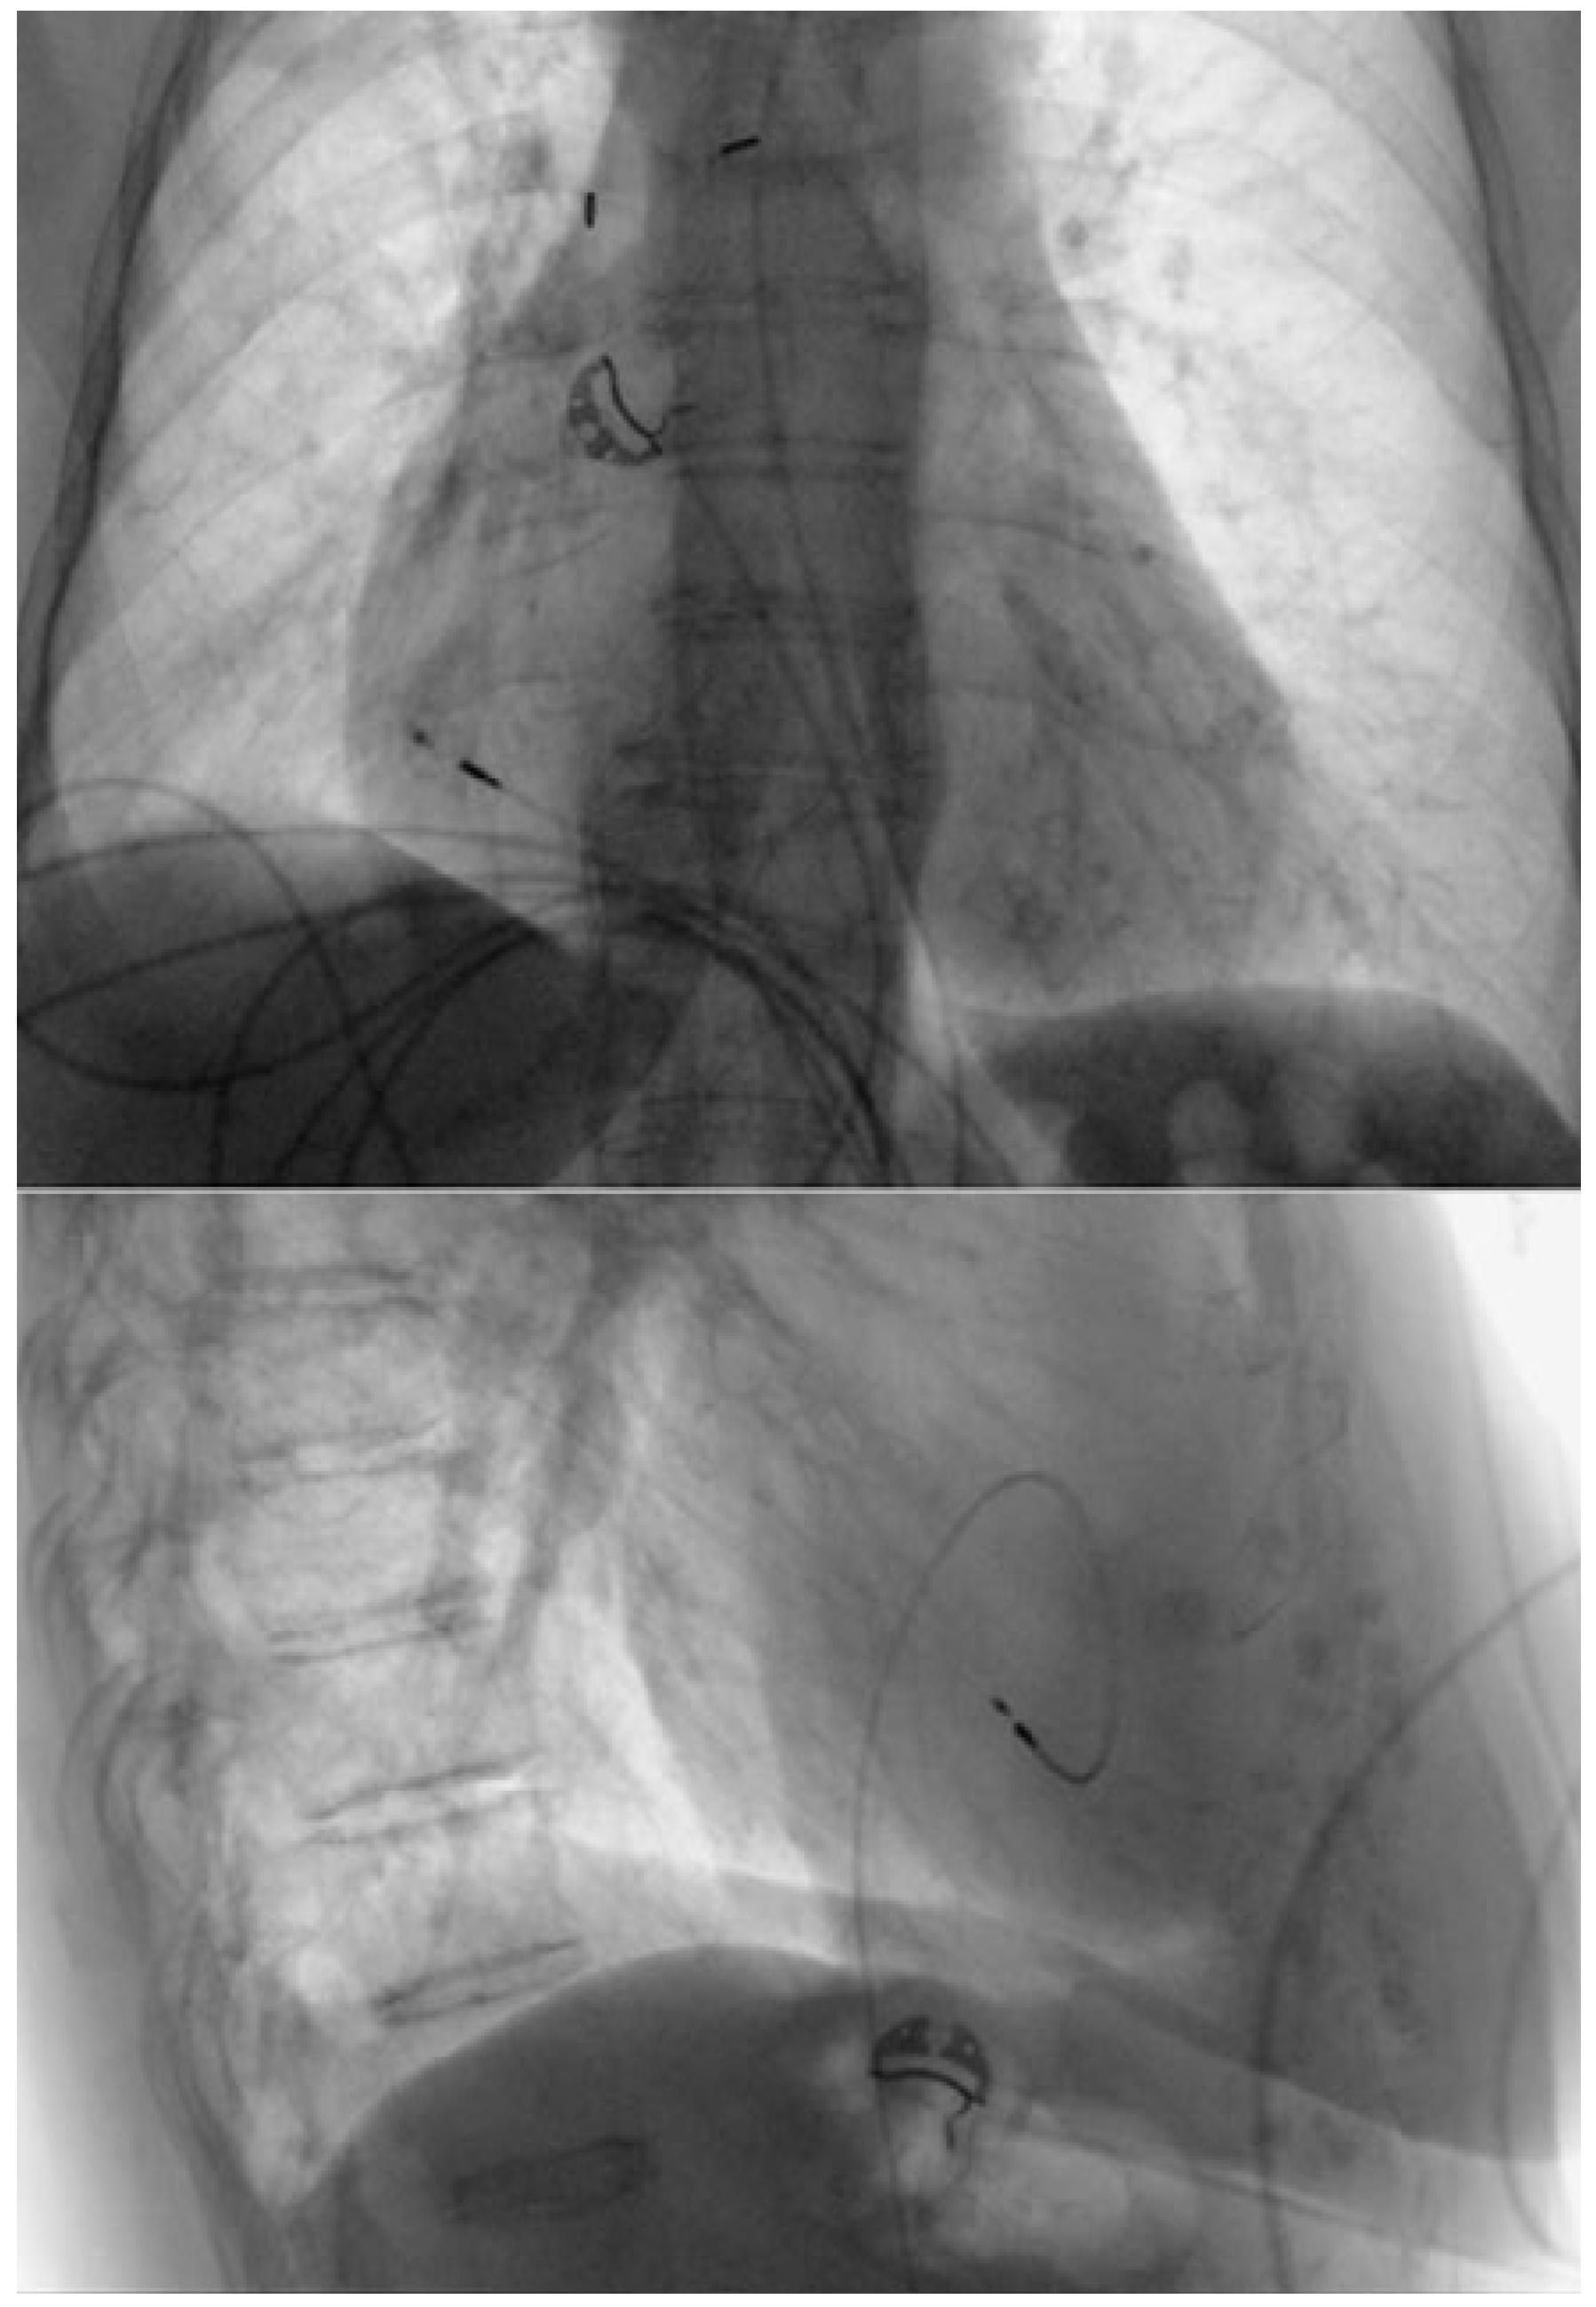

Pacemaker implantation: The right femoral vein was punctured in the groin, approximately 3 cm below the iliac ligament. A deflectable 8.4F guiding catheter (Medtronic® Minneapolis, MN, USA) was advanced over a 0.35 inch guidewire into the right atrium. A 69 cm Medtronic Select Secure 3830 lead was implanted in the right atrial appendage (Figure 2 and Figure 3). This is a 4.1 French lumenless fixed-helix active-fixation pacing lead that requires a guiding catheter for positioning. This model was chosen because of its length (59 cm and 69 cm available), its stability, and its high flexibility and tensile strength to accommodate increased stress due to hip flexion. The electrical parameters were normal and atrial pacing at 130 bpm revealed 1:1 conduction (with normal QRS width). For this reason, and to avoid excess foreign body material, a ventricular lead was not implanted. The lead was connected to a Medtronic Relia SR pacemaker, which was placed in a pocket in the upper anterior thigh. The wound was closed with resorbable subcuticular monofilament suture and a waterproof dressing was applied. The patient was discharged on the day after the procedure, with the device programmed to AAIR 60– 120 bpm. The wound healed well, without any discomfort caused by the generator pocket (Figure 4). The patient had marked symptomatic improvement, with rate histograms showing good adaptation despite the unusual generator location (Figure 5). Follow-up for more than 4 years has been uneventful, with stable electrical parameters.

Figure 3. Chest X-ray of the pacing lead implanted in the right atrium via femoral venous access.